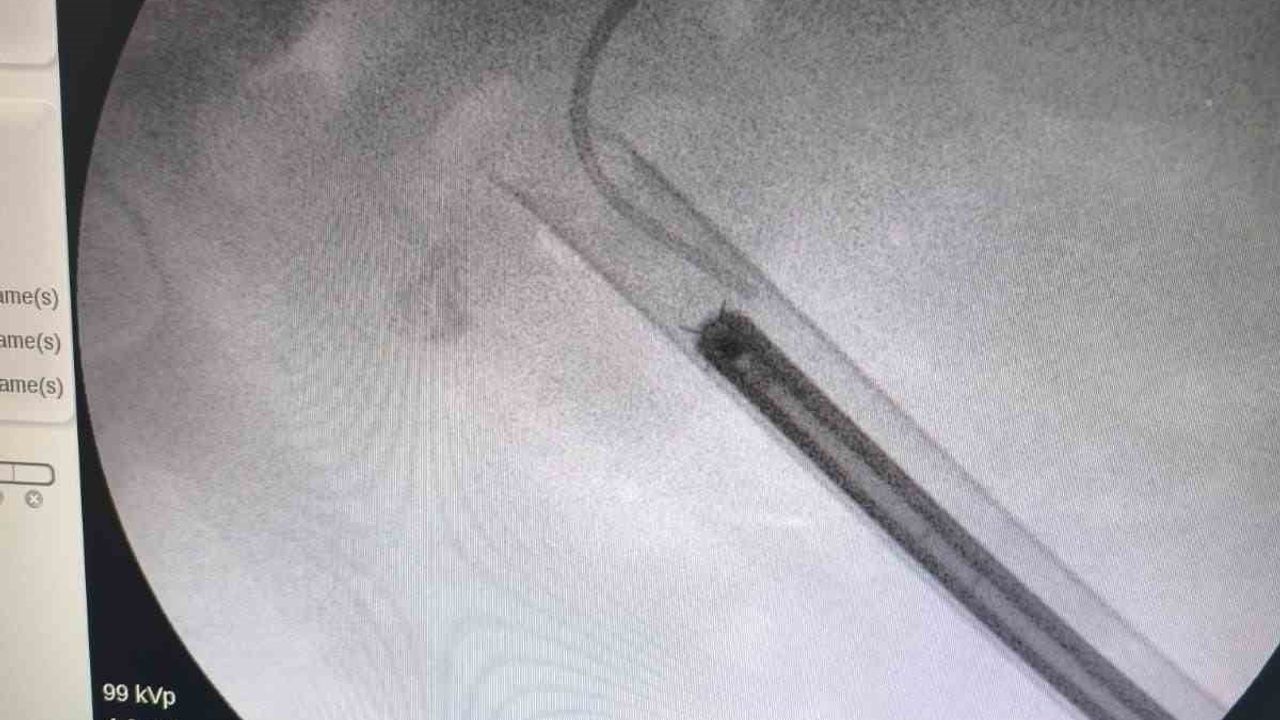

Üroloji uzmanı Dr. Miraç Ataman tarafından gerçekleştirilen müdahalede, taşın temizlenmesi için Perkütan Nefrolitotomi (PCNL) yöntemi tercih edildi. Bu yöntemde ciltten küçük bir giriş yapılarak endoskopik cihazlarla taş parçalanıp çıkarıldı. PCNL, özellikle çapı 2 cm'den büyük ve kompleks yapılı taşlarda altın standart olarak kabul ediliyor.

Vaka özelinde modern cerrahi altyapı sayesinde ciltten tek giriş yoluyla operasyon gerçekleştirildi ve böbreğin taş yükü yaklaşık 1,5 saatlik bir seansta başarıyla temizlendi. Dr. Ataman, operasyonun hem tıbbi hem de toplumsal sağlık açısından önemli bir başarı olduğunu vurguladı.